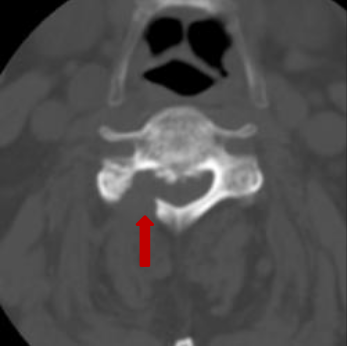

术前脊髓造影后颈椎CT。

颈椎间盘突出明显。